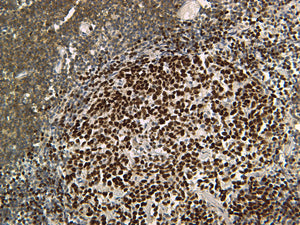

Cat lymph node stained with CD3e [VMAB0307]; 40X.